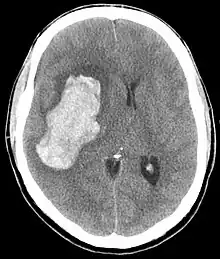

Saignement intra-parenchymateux avec œdème

L'hypertension artérielle maligne est définie par une élévation importante de la pression artérielle s'accompagnant d'une souffrance viscérale (défaillance cardiaque, rénale, neurologique...) avec à l'examen du fond d'œil une rétinopathie hypertensive au stade III ou IV. Il s'agit d'une urgence médicale.

En général, les valeurs de pression artérielle systolique sont très élevées sans qu'il y ait de valeur seuil (200 à 300 mmHg), par contre en termes de diastolique, on retrouve des valeurs supérieures à 120 mmHg voire 130 mmHg. L'évolution ou les variations tensionnelles peuvent également être importantes.